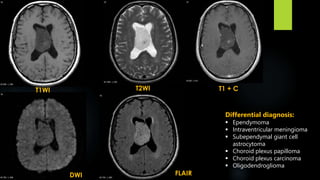

Central Neurocytoma

 WHO Grade II neuroepithelial intraventricular tumour

 typically seen in young patients (16-40 years of age), and generally have a good prognosis

 accounts for less than 1% (0.25-0.5%) of intracranial tumours

 symptoms of increased intracranial pressure, headaches being most frequent, or seizures

 associated with sudden death secondary to acute ventricular obstruction

 sudden presentation due to intraventricular haemorrhage

 Variant – ganglioneurocytoma

 Typical locations include:

- lateral ventricles around foramen of Monro (most common): 50%

- both lateral and 3rd ventricles: 15%

- bilateral: 15%

- 3rd ventricle in isolation: 5%

Central Neurocytoma (contd.)

 CT:

Central neurocytomas are usually hyperattenuating compared to white matter

Calcification seen in over half of cases, usually punctate in nature

Cystic regions are frequently present, especially in larger tumours.

Contrast enhancement is usually mild to moderate.

Accompanying ventricular dilatation often present.

 MRI:

T1 - isointense to grey matter, heterogenous

T1 + C - mild-moderate heterogeneous enhancement

T2/FLAIR - typically iso to somewhat hyperintense compared to brain

numerous cystic areas (bubbly appearance), many of which completely attenuate on FLAIR

Prominent flow voids may be seen

SWI – blooming

MRS – strong choline peak

Differential diagnosis:

 Ependymoma

 Intraventricular meningioma

 Subependymal giant cell

astrocytoma

 Choroid plexus papilloma

 Choroid plexus carcinoma

 Oligodendroglioma